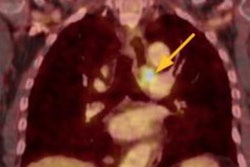

When it comes to tricky cases of vocal cord paralysis, CT rules supreme and is the imaging modality of choice. It's particularly effective for detecting any underlying malignancies in this patient group, prizewinning researchers from Barcelona, Spain, have asserted.

The team has shared its experiences of this field in today's top article. Their three clinical cases deserve a particularly close look.